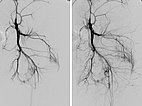

MIP-Rekonstruktion einer kontrastmittelunterstützen, dynamischen MR-Angiographie des Beckens und der Oberschenkel. Während auf der normalen rechten Seite hier noch eine arterielle Phase vorliegt, sind die Arterien und Venen der linken Seite massiv dilatiert und durch die multiplen arteriovenösen Fisteln des Parkes-Weber-Syndroms bereits die abführenden Venen kontrastiert.